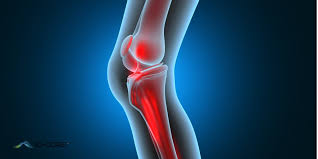

Knee Pain

We provide specialized knee pain treatment with advanced therapies and expert care to relieve discomfort, improve mobility, and restore joint health for a pain-free life.

We provide specialized knee pain treatment with advanced therapies and expert care to relieve discomfort, improve mobility, and restore joint health for a pain-free life.